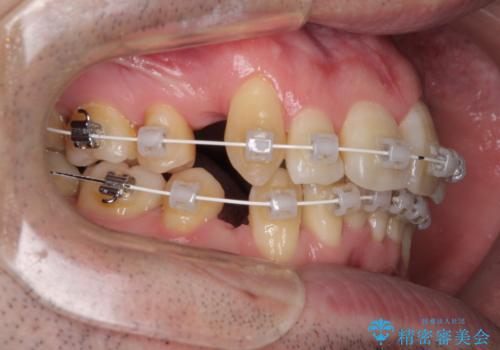

- 矯正装置

- 審美装置

治療開始直後は、あっという間に歯列が整い、すぐに終わるのではないかと思われましたが、治療の後半にブラックトライアングル解消のための処置を行ったため、当初予定していた2年半ほどの期間を要することとなりました。